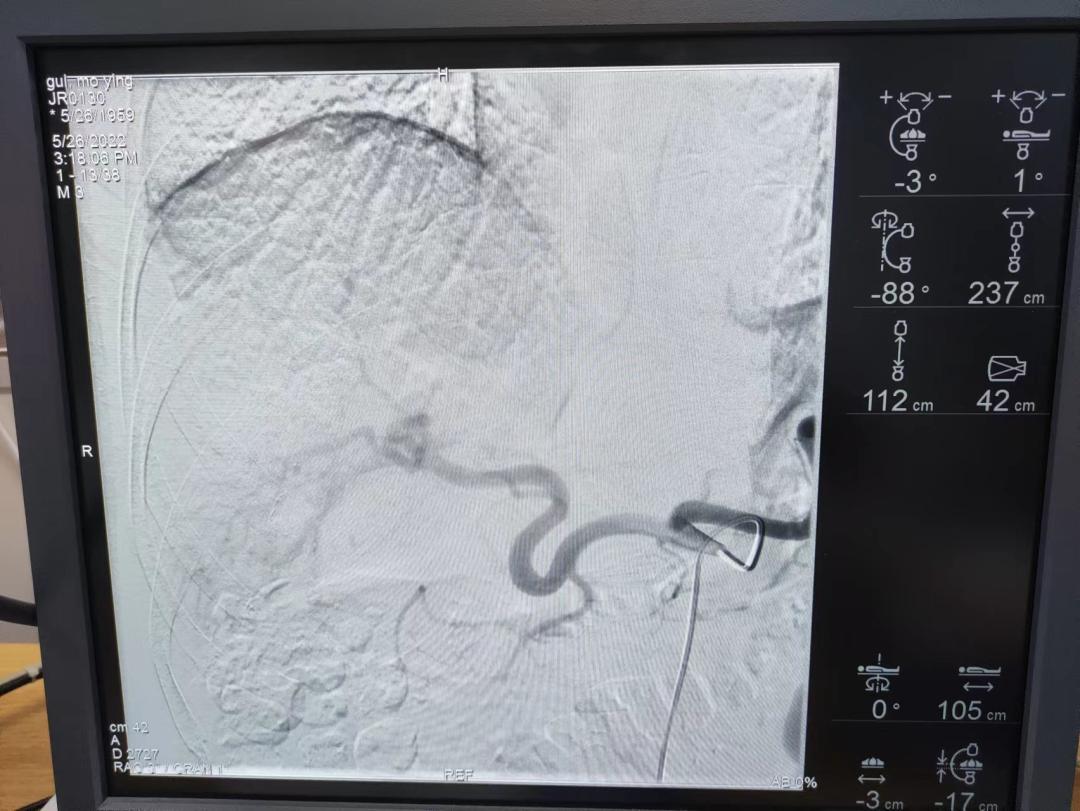

5月26日,在局麻状态下,肿瘤放疗中心主任郝萍在消化疾病中心廖东平医生的协助下成功为患者完成经导管肝动脉栓塞术。

手术过程中,由于患者为局麻状态,肿瘤放疗中心主任郝萍为了缓解患者情绪,一直在不断用轻松的言语与患者对话,经过郝萍主任耐心亲切的讲解,患者情绪逐渐平稳,积极配合医生的穿刺和治疗。

术中,由于瘤体较大,导致肝动脉迂曲、紊乱,导管难以通过,郝萍主任当即决定采用微导管超选(精准灌注药物)药物入肿瘤供血动脉,从而保障肿瘤完全受药以及肿瘤供血动脉准确栓塞,最终手术顺利完成。

郝主任介绍:肝血管瘤介入栓塞术,是通过栓塞供血动脉后瘤体内可形成血栓,血栓机化、纤维化使瘤体形成纤维瘤样结构而达到缩小、硬化血管瘤的目的,具有创伤小、恢复快、费用相对低等特点。手术过程中,由于患者肝动脉迂曲,导致导管难以进入,于是采取了微导管超选的方式进行介入治疗。

微导管超选择,简称“微管超选”,属于精准的介入治疗手段。在对患者实施治疗时,利用微型导管选择到肿瘤的每一条供血动脉,一个肿瘤对应—条动脉,然后将药物精确灌注到肿瘤部位,以此提高肿瘤内部的药物浓度,保证肿瘤完全受药及肿瘤供血动脉准确栓塞。相比传统的介入治疗方法,微管超选具有更精准,更彻底的治疗优势,进一步提高疗效,彻底“饿死”肿瘤。